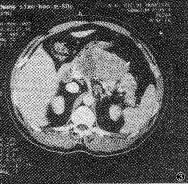

2.1.2 胰腺外异常CT表现:见表2。①胰周脂肪层模糊:30例。② 胰周大血管模糊:3 0例,肠 系膜上动脉癌栓形成2例。③ 肝内、外胆管扩张,胆囊增大:本组中胰头肿大伴肝内胆管扩 张30例,肝外胆管扩张32例,胆囊增大32例,胆总管扩张,绝大多数呈突然性狭窄截断。④ 转移性病变:胰周与大血管旁淋巴结肿大10例(图3),肝转移5例,腹水2例。

, http://www.100md.com 图3 胰体乳头状腺癌并腹膜后淋巴结转移。CT增强扫描示胰体部 轮廓明显增大,呈等、低混杂密度,腹腔动脉干左侧可见肿大的淋巴结